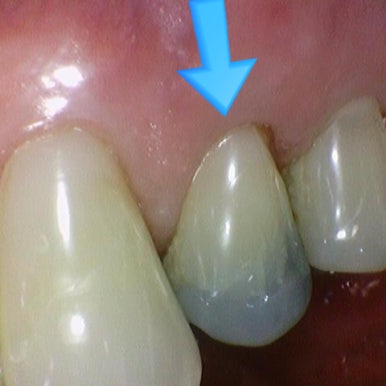

연세예감치과 지르코니아 크라운 전 후 (화살표치아)